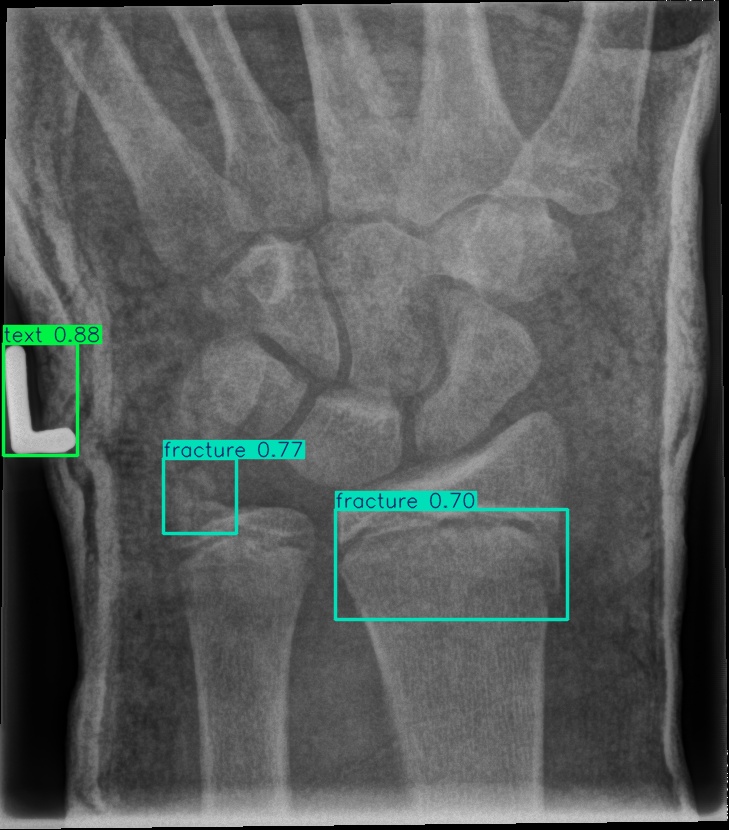

In this section, we first presented a comparison of the hardware requirements and the number of calculations for YOLOv11 and the proposed G-YOLOv11 in Table 2, followed by their plots of training and validation loss in Figure 6. Next, we reported the performance of these detectors on the GRAZPEDWRI-DX test set in Table 3. This is followed by qualitative and quantitative comparisons of detection using the YOLOv11l and proposed G-YOLOv11l detectors, as shown in Figure 8 and Table 4. Additionally, the FScore-confidence and PR curves are presented in Figure 7. Finally, we compared the proposed G-YOLOv11 with existing detectors in Table 5. For a fair comparison, we reproduced the results of the existing detectors using the same dataset division employed in our experiments.

Figure 8: Sample of five images from the GRAZPEDWRI-DX test set, displaying ground-truth and predicted bounding box annotations: (a-e): ground-truth annotations, (f-j): YOLOv11l annotations, and (k-o): G-YOLOv11 annotations.

Table 4: Confidence scores predicted by YOLOv11l and the proposed G-YOLOv11l detectors for five images from the GRAZPEDWRI-DX test set, PR: pronator sign, FP: False positive.

Figure number Class name Confidence score predicted Confidence score predicted

by YOLOv11l by our G-YOLOv11l

8(a) soft tissue, fracture, metal, text -, 0.670.67, 0.860.86, 0.830.83 -, 0.700.70, 0.890.89, 0.840.84

8(b) fracture, text 0.780.78, 0.710.71 0.790.79, 0.730.73

8(c) fracture, text 0.820.82, 0.780.78 0.810.81, 0.790.79, (FP: pr 0.44)0.44)

8(d) fracture, fracture, text 0.770.77, 0.700.70, 0.880.88 0.760.76, 0.520.52, 0.890.89

8(e) fracture, periosteal reaction, text 0.760.76, 0.690.69, 0.760.76 0.750.75, 0.600.60, 0.760.76

The results in Table 4, derived from Figure 8, compares the confidence scores predicted by YOLOv11l and G-YOLOv11l detectors for five test images from the GRAZPEDWRI-DX dataset. Figure 8 contrasts ground-truth annotations with predictions from YOLOv11l and G-YOLOv11l. G-YOLOv11l shows slight improvements, such as higher confidence scores for "fracture" and "metal" in Figure 8(a) (0.700.70 and 0.890.89 vs. 0.670.67 and 0.860.86) and for "text" in Figure 8(b) (0.730.73 vs. 0.710.71). However, limitations include false positives, such as for "pronator sign" in Figure 8(c) (score 0.440.44), and lower confidence for some instances, as seen in Figures 8(d) and 8(e). While G-YOLOv11l demonstrates competitive performance, further refinements are required to improve its robustness.